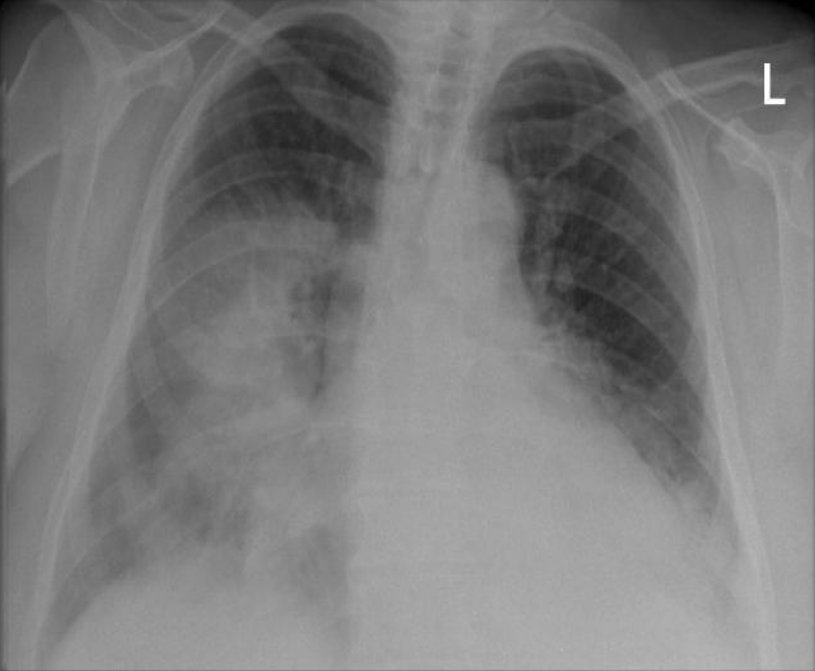

Difference Between Lung Infiltrate and Consolidation

When we breathe in, the inhaled air enters the trachea, the branches, and through progressively smaller airways reaches the alveoli – microscopic bubbles, where the gas exchange occurs. In some cases, the alveoli can fill up with a substance, for example with pus (e.g. in pneumonia), protein (in certain rare lung diseases), blood, water (e.g. pulmonary edema), cancer cells, etc. This substance is called lung infiltrate. The alveoli filled with infiltrate can be seen on a chest X-ray as an area, denser than the surrounding lung tissues, called consolidation.

What is Lung Consolidation?

The region of the lungs where the alveoli are filled with an atypical substance (i.e. lung infiltrate) instead of air is called lung consolidation. It is marked by hardening or swelling of the lung tissue and obstruction of the aeration in the affected area of the lung. Consolidation occurs in different diseases (when lung infiltrate occurs) and is an important radiologic sign.

Depending on the severity of the condition, the consolidation can cover a very small area of the lung surface and cause minimal symptoms, or cover a large part of the lung and cause a life-threatening condition.

Some of the common causes of consolidation are pneumonia, pulmonary edema, and pulmonary hemorrhage.

Pneumonia is the most common cause of lung consolidation. When there is an infection in the lungs, the body sends white blood cells to fight it. Dead cells and debris accumulate, creating pus that fills the small airways. Pneumonia is usually caused by bacteria or viruses, but can also be caused by fungi or other causes.

Congestive heart failure is the most common cause of pulmonary edema. When the heart cannot pump enough to keep the blood moving, it returns to the blood vessels in the lungs. The increased pressure pushes fluid out of the blood vessels into the small airways.

Pulmonary hemorrhage is most often caused by vasculitis (inflammation of the blood vessels), which makes the blood vessels weak and causes blood to pass into the small airways.

[3]Image credit: https://commons.wikimedia.org/wiki/File:X-ray_lung_consolidation.jpg

[4]Image credit: https://commons.wikimedia.org/wiki/File:X-ray_of_ground_glass_opacities_of_pneumocystis_pneumonia.jpg